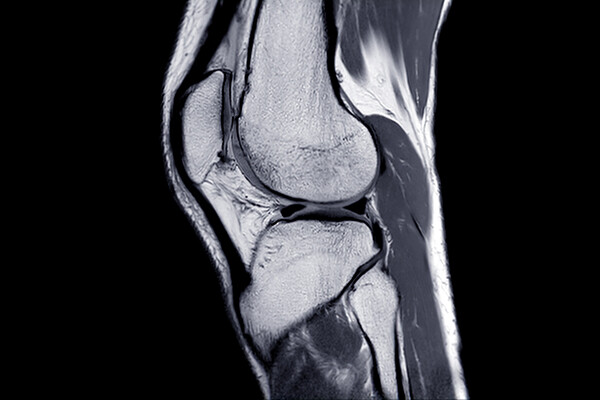

Using a magnetic field and hydrogels, a team of researchers in the Perelman School of Medicine have demonstrated a new possible way to rebuild complex body tissues, which could result in more lasting fixes to common injuries, such as cartilage degeneration. This research was published in Advanced Materials.

In humans, tissues like cartilage can often break down, causing joint instability or pain. Often, the breakdown isn’t in total, but covers an area, forming a hole. Current fixes are to fill those holes in with synthetic or biologic materials, which can work but often wear away because they are not the same exact material as what was there before. It’s similar to fixing a pothole in a road by filling it with gravel and making a tar patch: The hole will be smoothed out but eventually wear away with use because it’s not the same material and can’t bond the same way.

What complicates fixing cartilage or other similar tissues is that their makeup is complex.

“There is a natural gradient from the top of cartilage to the bottom, where it contacts the bone,” Zlotnick explains. “Superficially, or at the surface, cartilage has a high cellularity, meaning there is a higher number of cells. But where cartilage attaches to the bone, deeper inside, its cellularity is low.”